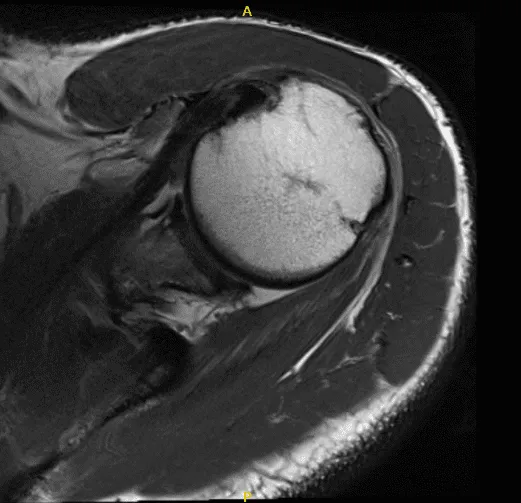

MRI of left shoulder

His MRI showed a complete tear of the supraspinatus tendon with 8 mm of medial retraction. Mild infraspinatus and long head biceps tendinosis and mild subacromial/subdeltoid and sub coracoid bursitis.

Mild AC arthrosis and degeneration of the superior posterior superior labrum. We discussed surgical and non-surgical treatment and the patient refused the surgery and wanted to give the conservative medication. Tramadol was prescribed for pain management.